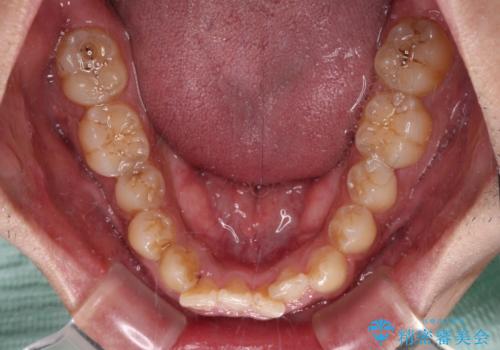

- 前歯のデコボコを気にして来院された患者様です。

前歯が90度近く捻れていたため、しっかりと治すことを考えるとワイヤー矯正の方がおすすめではありましたが、本人の希望によりインビザラインを用いて矯正治療を行うこととしました。

途中2年強の来院がなく、改善されていたデコボコが元に戻ったり、装着時間が不足しており前歯のデコボコは十分に改善することはできませんでしたが、5年間の有効期限内で可能な限り歯列を整えることができました。